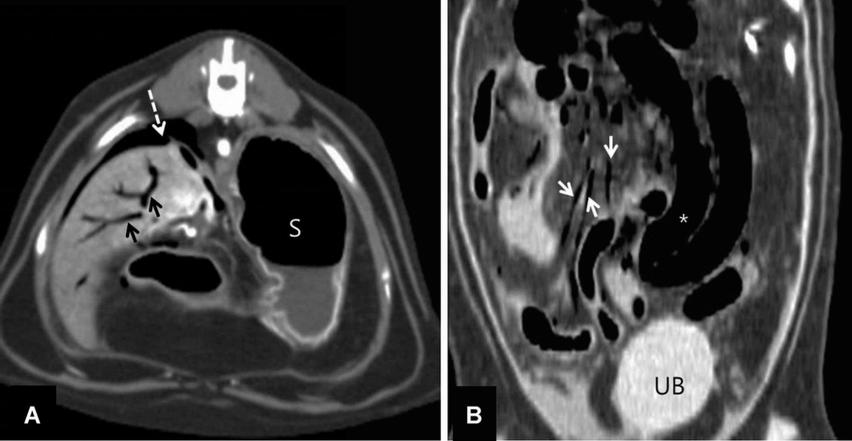

Portal venous gas within the liver

Peritoneal free gas

Gas within the mesenteric arteries

Severely distended, thin walled bowel loops

Imaging diagnosis - Acute mesenteric ischemia secondary to HCM in a cat - VRU 56.4.